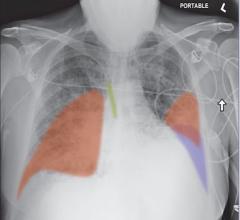

May 15, 2020 — Chest X-rays performed on young and middle-aged adults with COVID-19 when they arrive at the emergency ...